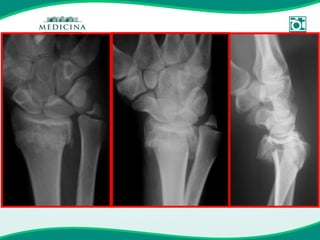

Fratura instável & Osteoporose

Fratura Instável

Fixação Interna

MAU RESULTADO CLÍNICO OSTEOPOROSE

MAU RESULTADO CLÍNICO FRATURA DE ALTA ENERGIA